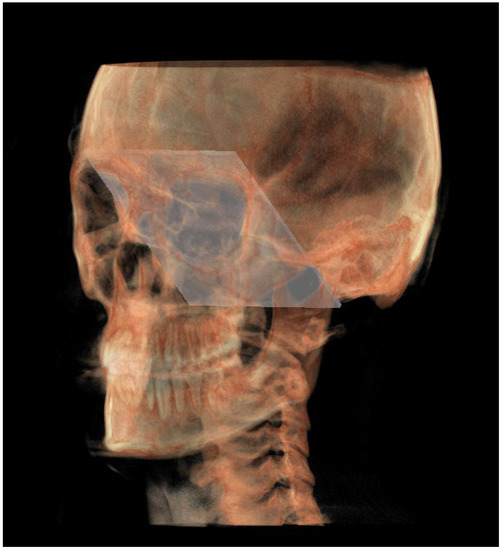

- The mandibular ramus plane (MR) (Figure 5) was identified by the following points: the middle points between the right and left condylion (mCo) and the right Gonion (rGo) and left Gonion (lGo). To adequately locate the mCo, it is advisable to draw a line on the frontal view from the right condylion to the left one to have a reference along which measure the mid-distance;

- The functional occlusal plane (FOP) (Figure 6) was identified by the posterior occlusal contact right side (rPoc), posterior occlusal contact left side (lPoc) and the middle point between the right and left anterior occlusal contact (mAoc). To adequately locate the mAoc, it is advisable to draw a line on the transversal view from the right mesial premolar contact to the left one to have a reference along which measure the distance.

| MR neutral (MRn) | Plane passing through the mCo, rGon and lGon |

| FOP neutral (FOPn) | Plane normal to the PMn passing through rPoc and lPoc |

| Construction plane through Ba (CPBa) | Construction plane passing through Ba and parallel to the PM |

| Construction plane through Co (CPCo) | Construction plane passing through the mCo and parallel to the PMn |

| GoP | Gonion plane: plane passing through rGo and lGo normal to PMn |